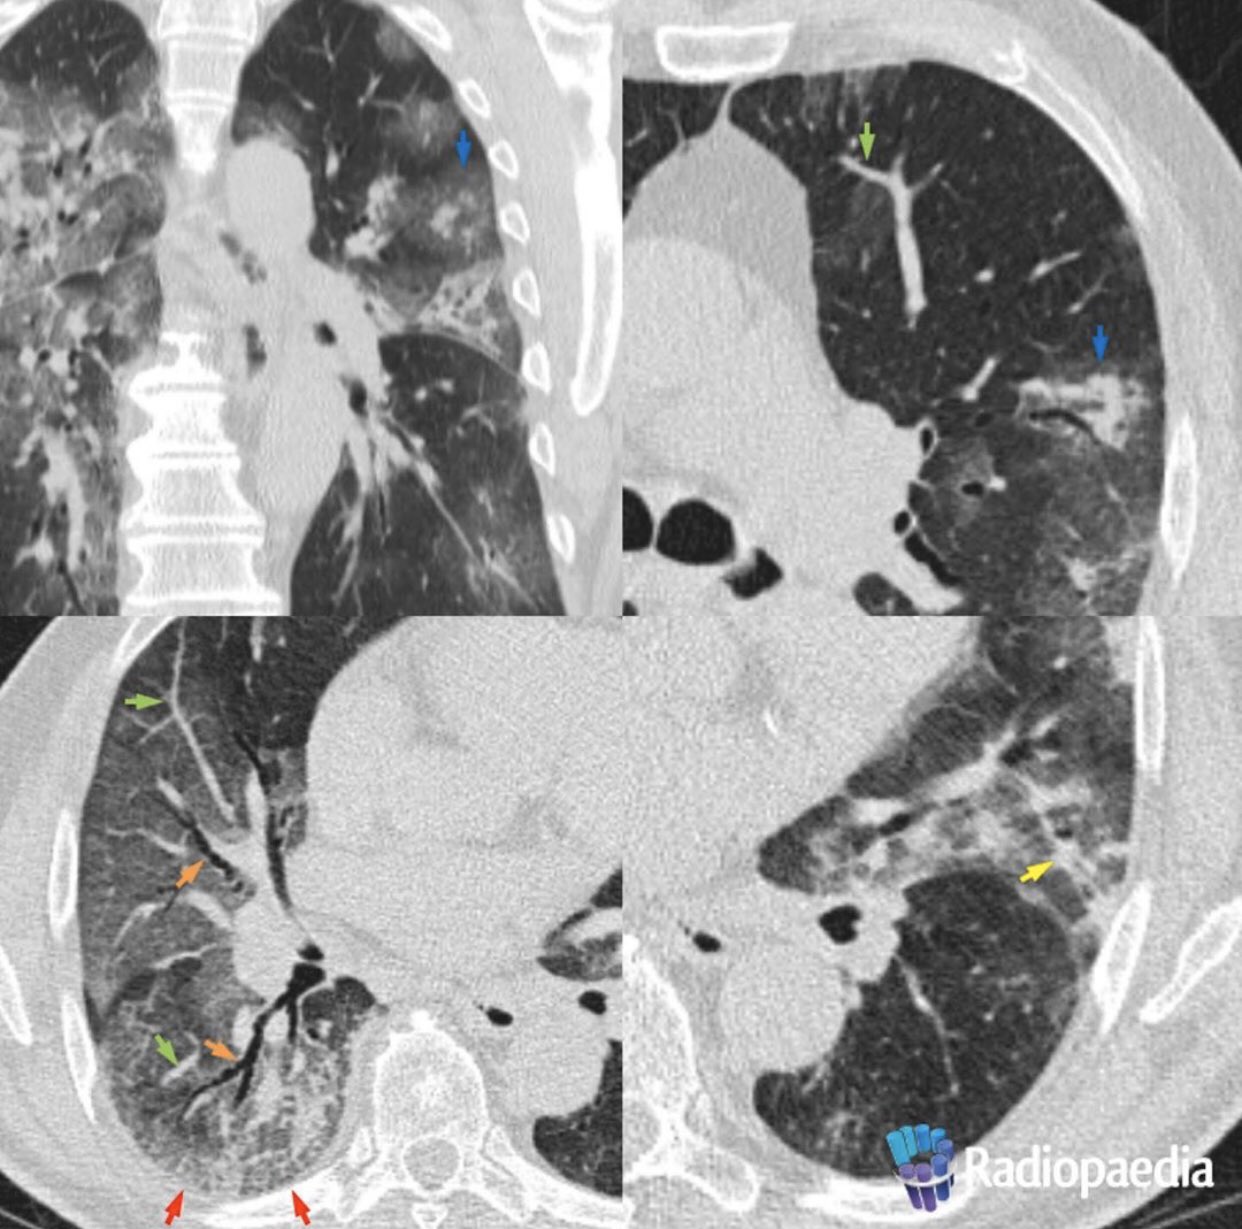

Bilateral multilobar peripheral ground glass opacities in both lungs predominantly in mid to lower zones.

Partial consolidations along the bronchovasular bundles surrounded by ground glass opacities ggo superimposed inter and intralobular septal thickening crazy paving pattern in the right lower lobe. The severe acute respiratory syndrome sars is a zoonotic illness caused by severe acute respiratory syndrome related coronavirus sars cov 1 a coronavirus. Extensive patchy bilateral multi lobar ground glass opacities ggo predominantly peripheral distribution in the left lung peripheral and central distribution in the right lung. Is case demonstrates acute extensive bilateral ground glass opacities in an immunocompromised patient with differentials including pneumocystis jirovecii and cmv with the latter favored given the elevated cmv viral load.